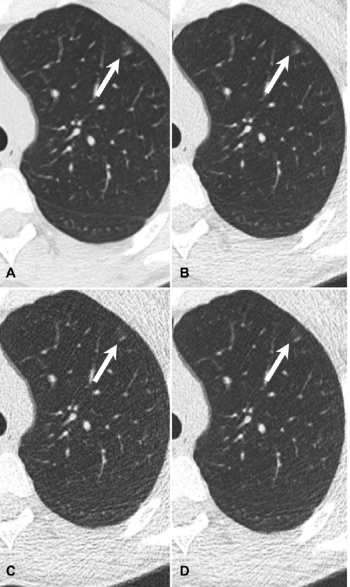

Dropping National Lung Cancer Screening radiation dose by two-thirds can yield images of diagnostic quality of solid lung nodules.